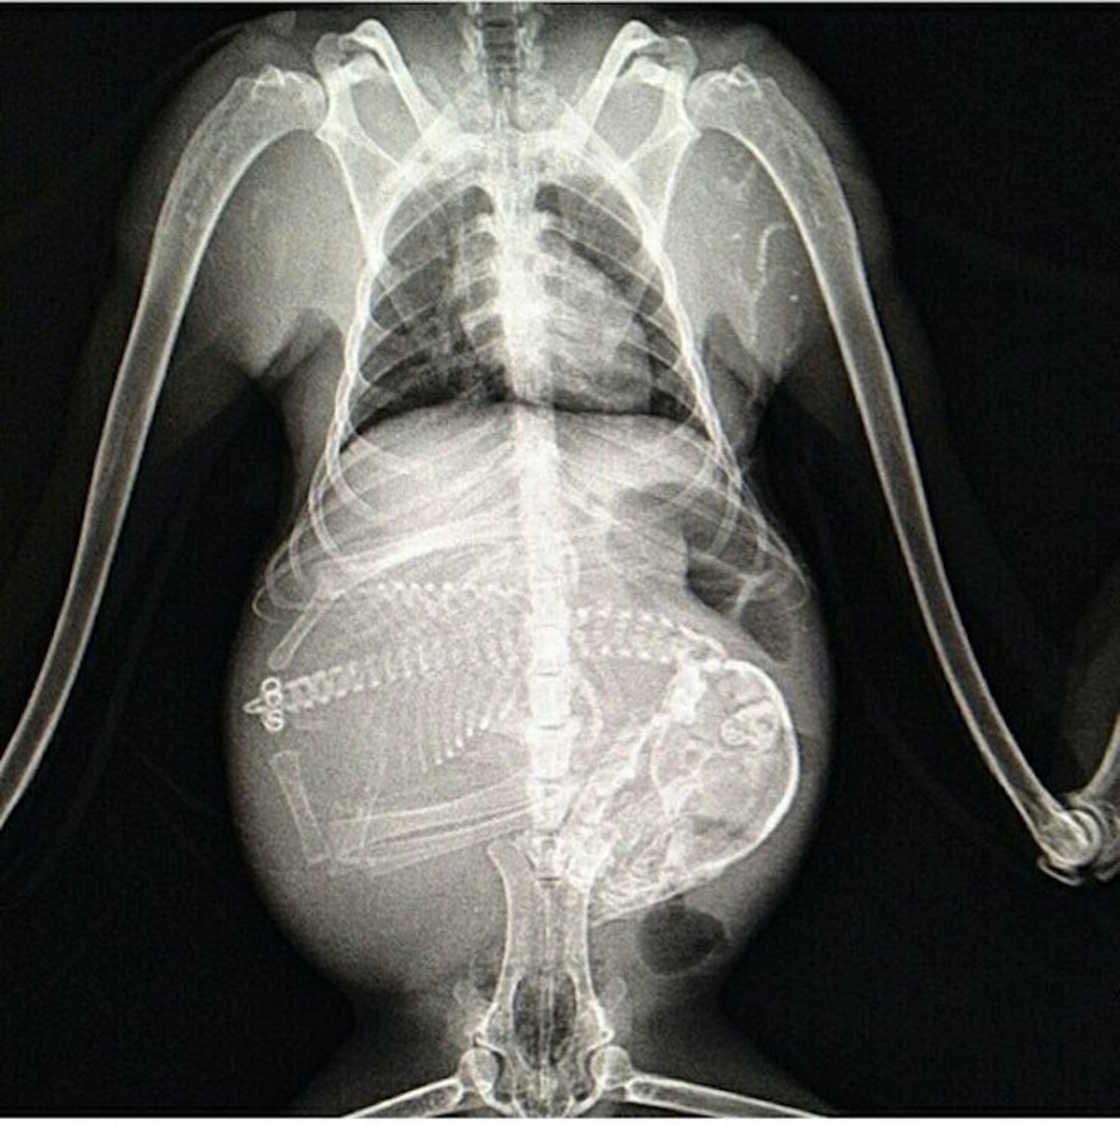

Рентгеновский эффект создает фантастические композиции в этих фотографиях девушки, чье тело становится прозрачным, демонстрируя скелет и внутренние органы. Она позирует в разных позах, ее силуэт светится загадочным свечением. Каждый кадр передает атмосферу научной фантастики и медицинского искусства. Ее кожа кажется полупрозрачной, позволяя увидеть кости и мышцы. Фотографии рассказывают о хрупкости человеческого тела и его внутренней красоте. Девушка то стоит в задумчивости, то делает грациозное движение. Эти иллюстрации вдохновляют на размышления о человеческой анатомии и уязвимости. Каждая картинка - это момент прозрения, когда внешнее уступает место внутреннему. Девушка воплощает образ современной Медузы, сочетающей красоту и загадочность.

Сквозь материю: тайны анатомии